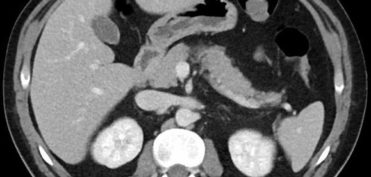

אבחון צילומי דימות – MRI ו-CT – בעזרת תוכנת מחשב

מאת: עופר בן חורין. כאשר מבצעים צילומים, לרוב מעורבת בכך תוכנה, ואז הצילומים עוברים דרך תקשורת מחשבים אל תחנה בה יושב הרופא וכך הם מפוענחים. האם תוכנה חכמה יכולה להחליף, לעזור לרדיולוג או לפחות לספק חוות דעת שנייה לגבי צילומים? התשובה, משמע האפשרות של אבחון צילומי דימות…לחצו להמשך קריאה